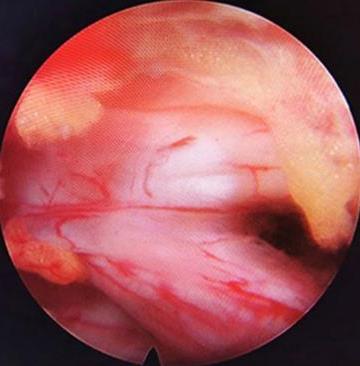

• 不同入路脊柱内镜手术治疗L4/5节段脱垂型腰椎间盘突出症的疗效比较

摘要:目的 观察经椎间孔入路内镜下腰椎间盘切除术(TELD)和经椎板间入路内镜下腰椎间盘摘除术(IELD)治疗L4/5节段脱垂型腰椎间盘突出症(LDH)的临床疗效。方法 回顾性分析2020年11月-2022年11月该院采用脊柱内镜手术治疗的75例L4/5节段脱垂型LDH患者的临床资料。根据手术入路的不同,将患者分为TELD组(53例)和IELD组(22例)。比较两组患者的手术情况和术后疗效。结果 与TELD组比较,IELD组的手术时间明显缩短,术中透视次数明显减少,差异均有统计学意义(P < 0.05);两组患者住院时间和并发症发生率比较,差异均无统计学意义(P > 0.05)。所有患者术后均获得12~19个月的随访。两组患者末次随访时的视觉模拟评分法(VAS)评分和Oswestry功能障碍指数(ODI)明显低于术前,且IELD组明显低于TELD组,差异均有统计学意义(P < 0.05)。按照突出物和神经根的不同位置进一步分析,两组肩上型患者(TELD组10例,IELD组6例)末次随访时的VAS评分和ODI明显低于术前,且IELD组末次随访时的VAS评分明显低于TELD组,差异均有统计学意义(P < 0.05);两组腋下型患者(TELD组8例,IELD组16例)末次随访时的VAS评分和ODI明显低于术前,且IELD组明显低于TELD组,差异均有统计学意义(P < 0.05);35例肩前型患者经TELD术后,末次随访时的VAS评分和ODI明显低于术前,差异有统计学意义(P < 0.05)。按照突出物的不同Lee分区进一步分析,两组Lee Ⅲ区患者(TELD组44例,IELD组10例)末次随访时的VAS评分和ODI明显低于术前,且IELD组的ODI明显低于TELD组,差异均有统计学意义(P < 0.05);两组Lee Ⅳ区患者(TELD组9例,IELD组12例)末次随访时的VAS评分和ODI明显低于术前,且IELD组明显低于TELD组,差异均有统计学意义(P < 0.05)。结论 采用TELD和IELD治疗L4/5节段脱垂型LDH,均可获得较满意的减压效果,但IELD的手术时间相对较短,X线透视次数较少,且对肩上型、腋下型、Lee Ⅲ区和Lee Ⅳ区的减压效果更有优势。